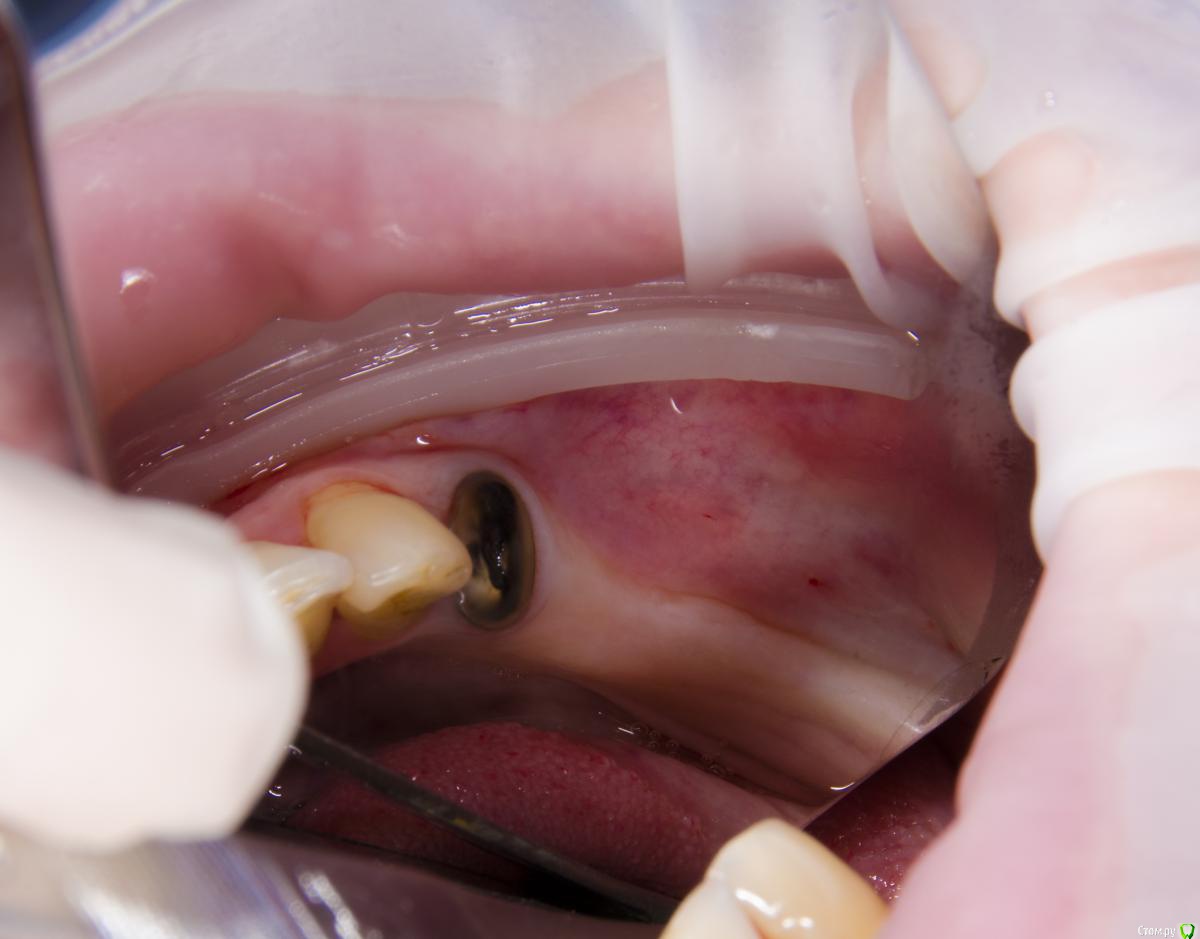

Тимур86 Опубликовано 31 января, 2017 Поделиться Опубликовано 31 января, 2017 Это,как я понял,конечный результат Ссылка на комментарий

kamranchick Опубликовано 1 февраля, 2017 Автор Поделиться Опубликовано 1 февраля, 2017 Это,как я понял,конечный результатДа тим. Ссылка на комментарий

Доктор Добрых Дел Опубликовано 31 января, 2017 Поделиться Опубликовано 31 января, 2017 Аугментата пожалели мне кажется, объёма не особо добавится. Почему винты сразу не захотели? Вроде кости много. Ссылка на комментарий